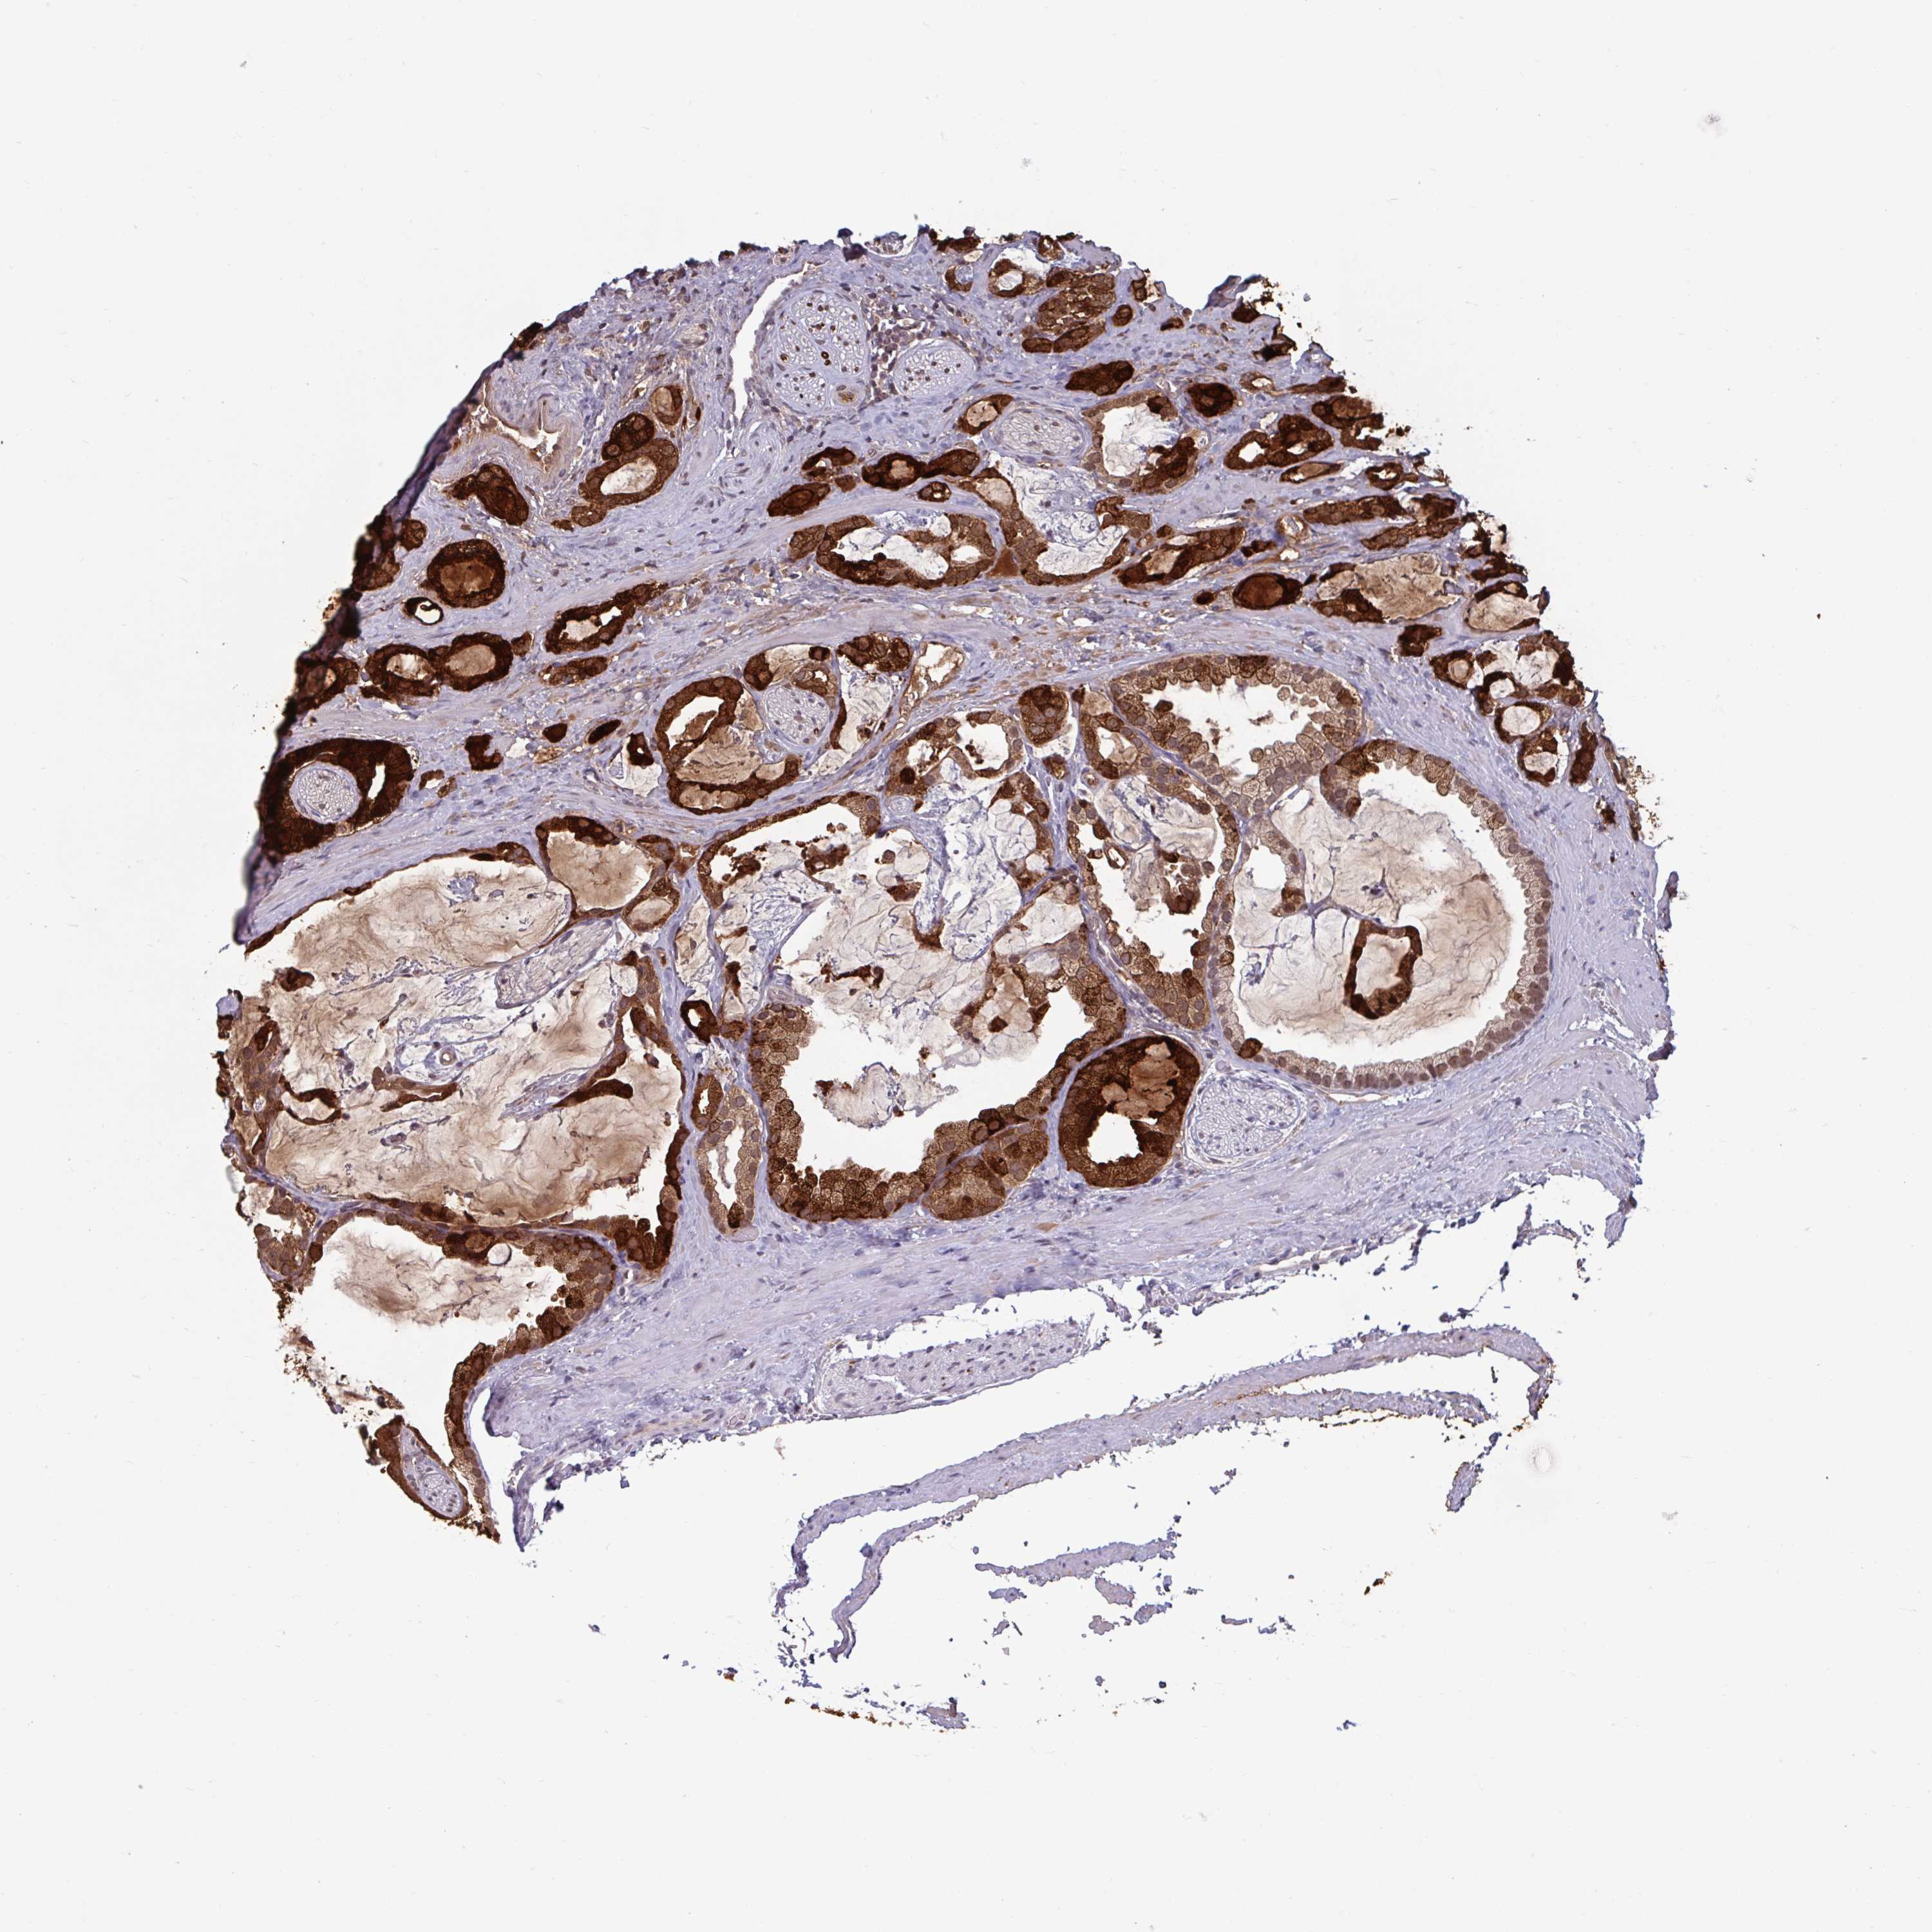

PROSTATE CANCER - Protein expressioni

A mouse-over function shows sample information and annotation data. Click on an image to view it in a full screen mode. Samples can be filtered based on level of antibody staining by selecting one or several of the following categories: high, medium, low and not detected. The assay and annotation is described here.

Antibody stainingi

Antibody staining in the annotated cell types in the current human tissue is reported as not detected, low, medium, or high, based on conventional immunohistochemistry profiling in selected tissues. This score is based on the combination of the staining intensity and fraction of stained cells.

Each image is clickable and will lead to virtual microscopy that enables deeper exploration of all samples and also displays staining intensity scores, fraction scores and subcellular localization as well as patient and tissue information for each sample.

Antibody HPA051257

Antibody CAB026357

Staining

High

Medium

Low

Not detected

Intensity

Strong

Moderate

Weak

Negative

Quantity

>75%

75%-25%

<25%

None

Location

Nuclear

Cytoplasmic/membranous

Cytoplasmic/membranous,nuclear

Adenocarcinoma, High grade

Adenocarcinoma, Medium grade

Adenocarcinoma, Low grade